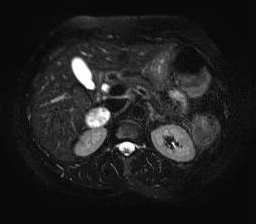

Wenn die Bestimmung der Plasma-Metanephrine wiederholt ein positives Ergebnis bringt, muss eine weiterführende Lokalisationsdiagnostik durchgeführt werden. Dies geschieht mittels bildgebender Verfahren wie der Sonografie und Computertomografie oder der Magnetresonanztomografie. Die nuklearmedizinische Methode der MIBG-Szintigrafie (Metaiodobenzylguanidin), bei der es sich um eine Substanz handelt, die sich in den betroffenen chromaffinen Zellen des Phäochromozytoms anreichert, dient zur Lokalisation von extraadrenal (= außerhalb der Nebennieren) gelegenen Tumoren. Für die Detektion von Metastasen stellt die sensitivste Methode die 6-[18F]-Fluorodopamin-PET (= Positronenemissionstomografie) dar. Die neueste und zuverlässigste nuklearmedizinische Methode zur Phäochromzytomdiagnostik ist das so genannte DOPA-PET.

| Bildgebende Verfahren beim Phäochromozytom | |